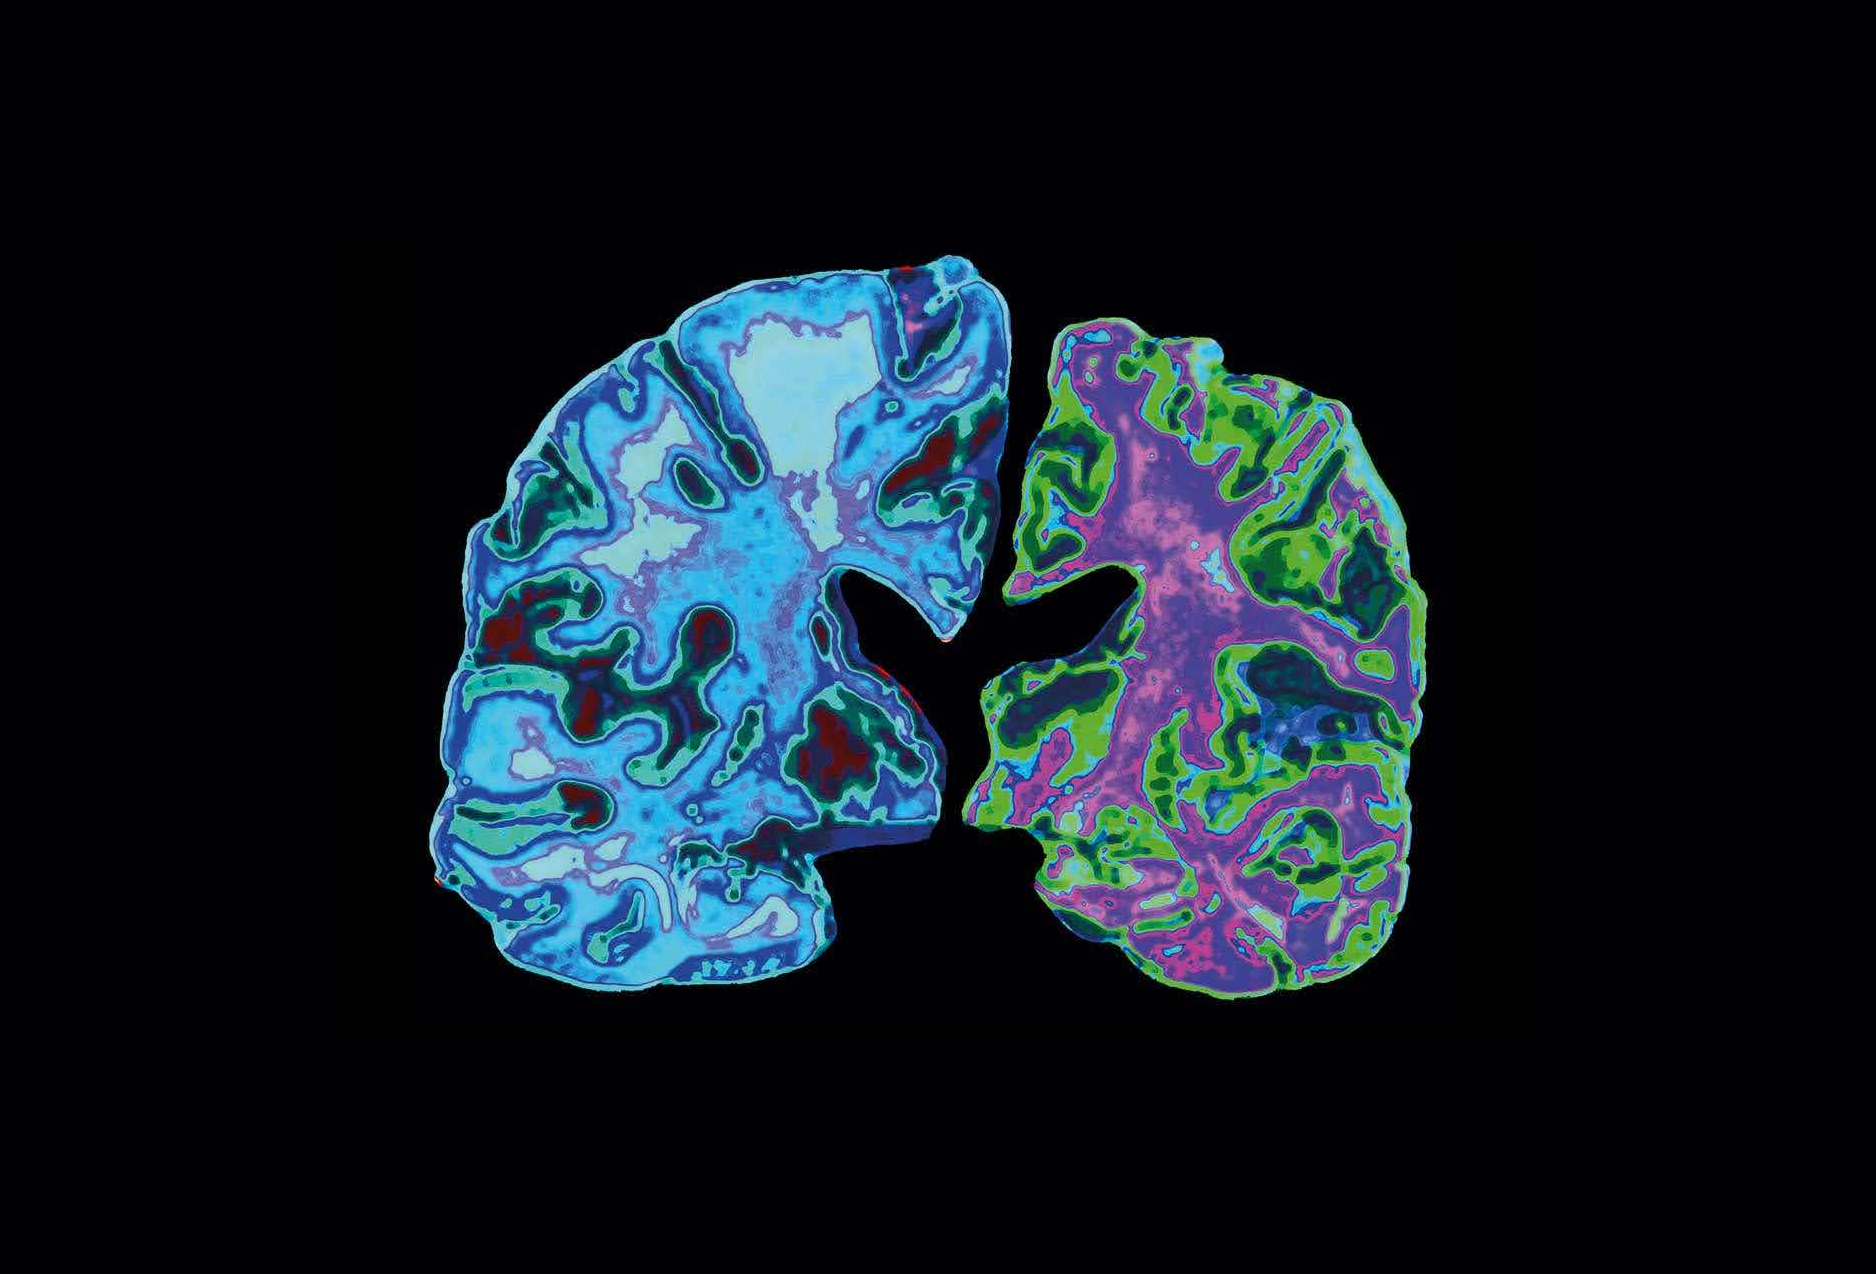

The Fight against Alzheimer’s

Alzheimer's is a disease characterized by memory loss and impaired reasoning. It's scary because there is no cure; once a person is diagnosed with Alzheimer's, it progressively worsens until they lose most of their memories.